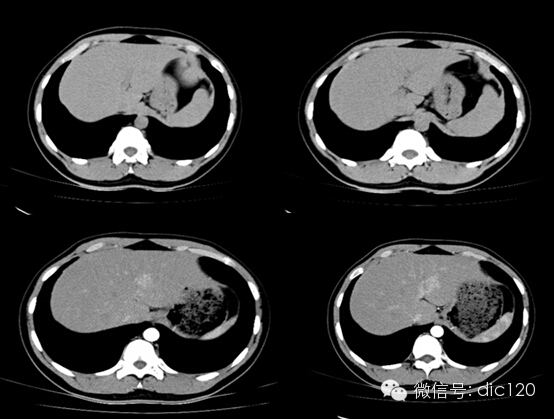

影像表現:CT平掃與正常肝組織呈等密度,密度均勻,動脈期病灶快速明顯均勻強化,中心見小片狀低密度影(瘢痕),門脈期及延遲期對比劑快速退出呈等密度,中央低密度影延遲強化。MRI腫塊T2WI為稍高信號,中央高信號。動態增強掃描動脈期均顯著增強,門脈期輕度增強,延遲期瘢痕強化。

FNH具有離心性血液供應及二條血液引流途徑。FNH的典型CT表現包括增強早期腫瘤呈彌漫均勻強化,在門靜脈期或門靜脈后期成等密度,病灶內可見中心低密度瘢痕及輻射狀分隔,腫瘤周圍有薄而不完整的包膜樣血管。瘢痕是FNH 另一個重要影像學表現,尤其是延遲掃描瘢痕強化為其特征。